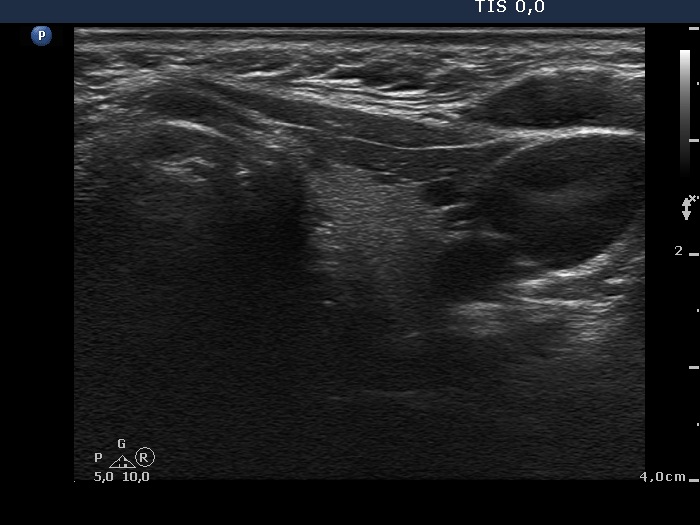

Right lobe, longitudinal scan

Left lobe, transverse scan. Tiny hypoechogenic foci are demonstrated in the ventrolateral part of the lobe.